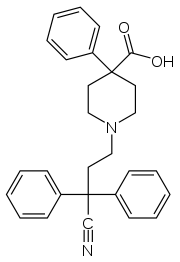

Pirinitramides

Structures

| Pirinitramides | ||||

|---|---|---|---|---|

|

| |||